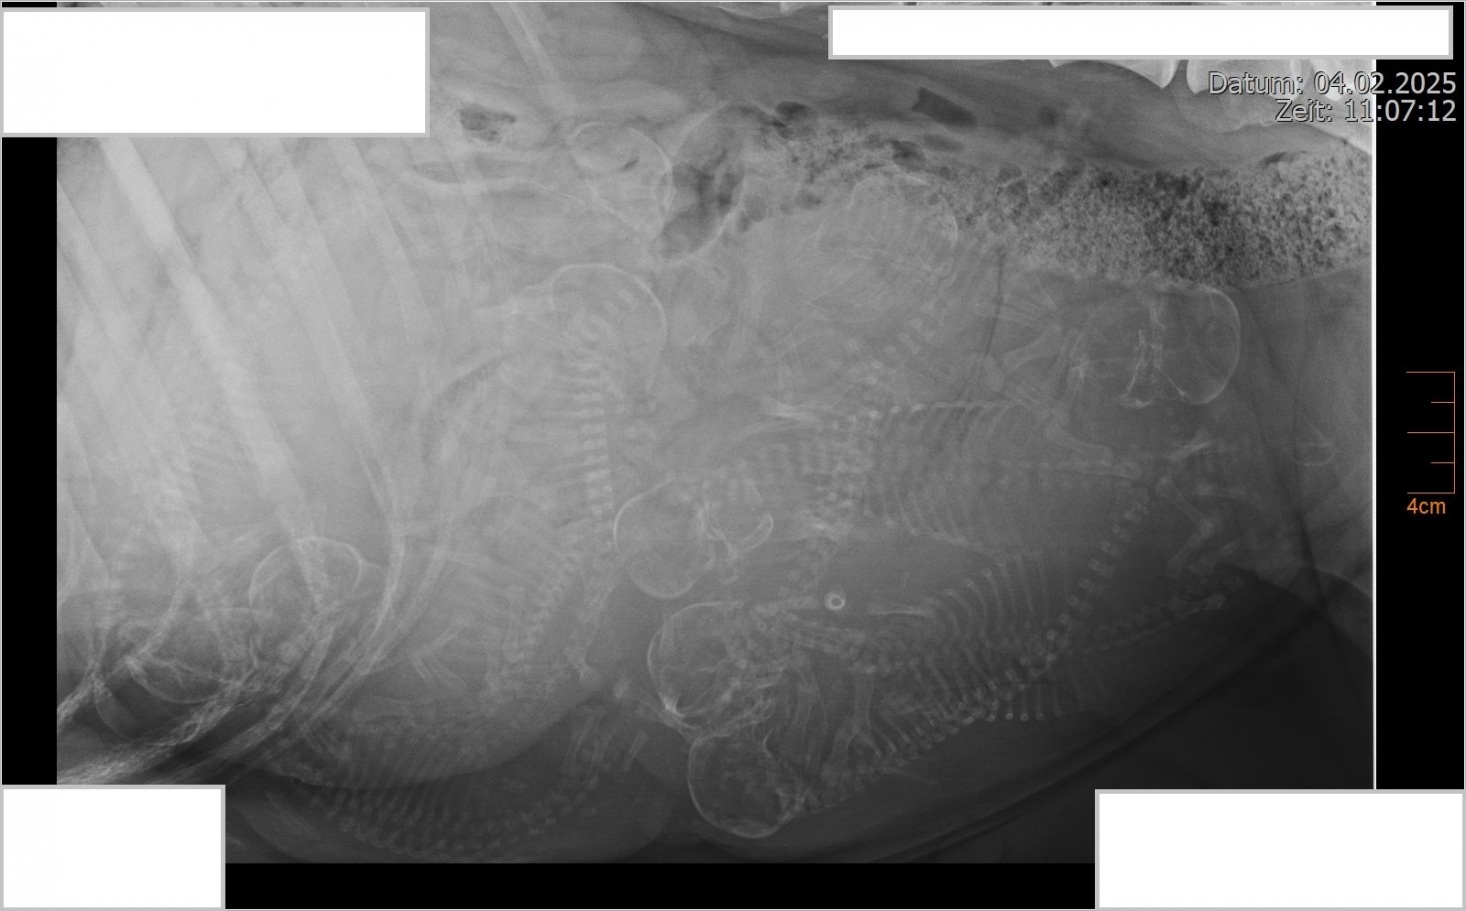

So langsam wird es eng in Bailey's Bauch, wir freuen uns so sehr auf die kleinen Welpen!

Wir freuen uns dass die Deckung mit Bailey und Brut geklappt hat und sie trächtig ist! Wir erwarten die Welpen Mitte Februar 2025!